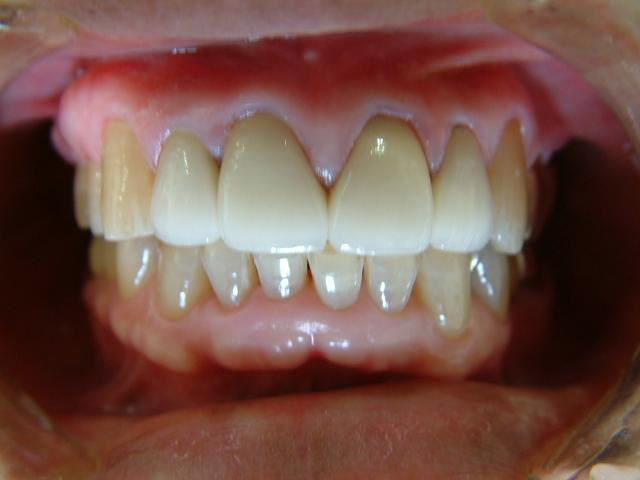

初診の状態とセット時の状態

初診と最終補綴物

患者さんにも満足して頂けた最終補綴物 |